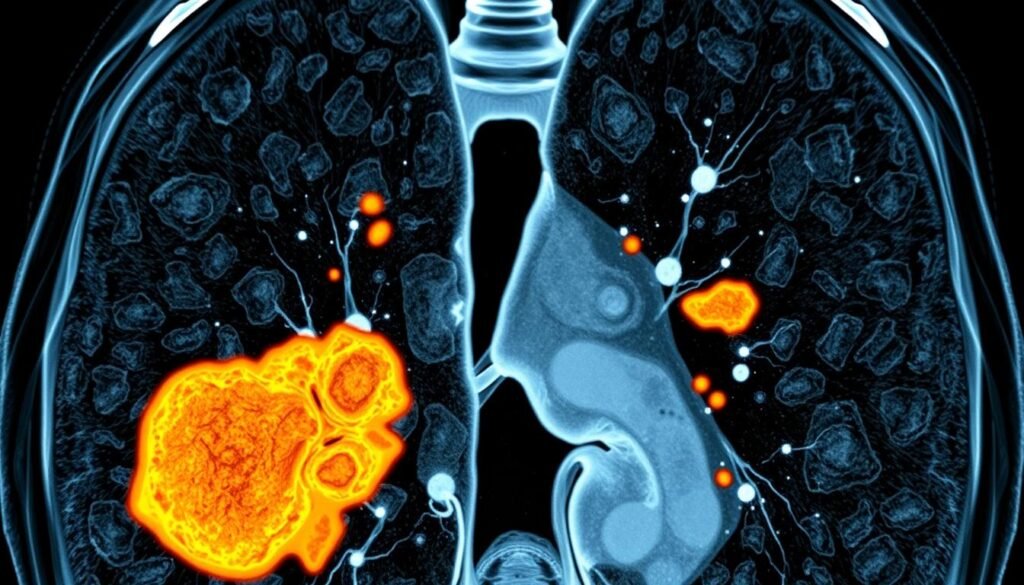

CT Imaging Features of Small Cell Lung Cancer

Understanding CT images of Small Cell Lung Cancer (SCLC) is key to proper diagnosis and planning treatment. Imaging techniques help doctors see signs that show SCLC’s presence and how far it’s spread. This helps them fight this tough cancer better.

Common Findings on CT Scans

On CT scans, SCLC shows up in specific ways. Some familiar signs are:

- Centrally located masses: Often, SCLCs are big masses in the lung’s center, near important airways.

- Mediastinal involvement: These cancers tend to spread to nearby areas in the chest.

- Lymphadenopathy: Swollen lymph nodes, especially around the lungs and chest, signal the disease is advancing.

- Pleural effusions: Fluid in the lung area also suggests SCLC, together with other signs.

Classification of SCLC on Imaging

Categorizing SCLC on imaging is critical for choosing the best treatment approach. The focus is on where the tumor is and if it’s spread to the mediastinum. CT scans give doctors detailed info to plan the treatment that fits each patient’s situation.